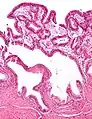

Micrografia da colesterolose da vesícula biliar.